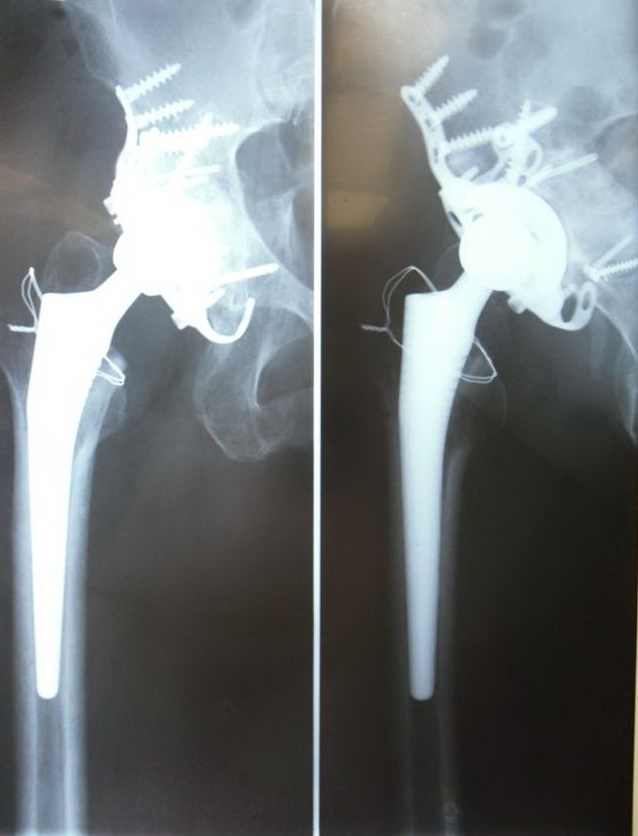

Ортопедическое отделение Главного военного клинического госпиталя им. акад. Н.Н.Бурденко занимается вопросами эндопротезирования крупных суставов более 30 лет. Мы прошли весь тернистый путь проб и ошибок в освоении этой специальности, познали горечь неудач и радость успеха. В отделении разработаны и запатентованы: уникальная методика двухэтапного эндопротезирования тазобедренных суставов, новые способы костнопластического замещения значительных дефектов вертлужной впадины при ревизионных операциях.

Выполняются операции эндопротезирования тазобедренного, коленного, локтевого и плечевого суставов при онкологической костной патологии и посттравматических деформациях.

В последние годы мы активно занимаемся проблемой эндопротезирования тазобедренного сустава у молодых пациентов, в том числе при врождённой патологии (дисплазии) используя при этом новейшие высококачественные долговечные эндопротезы.